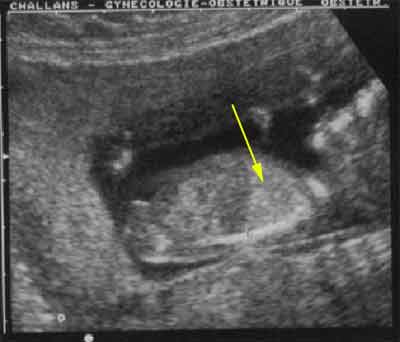

Coupe longitudinale